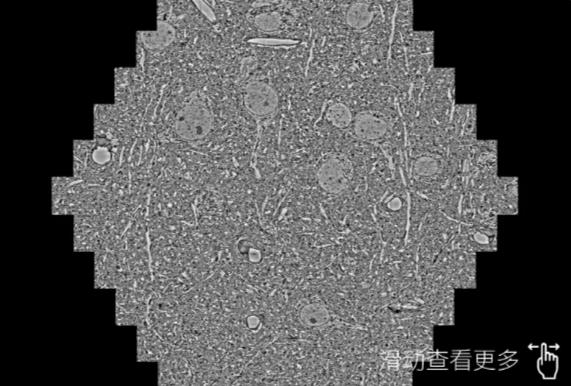

鼠脑切片。左图使用涪陵蔡司涪陵扫描电镜MultiSEM706对165μmx143pm面积区域成像,耗时仅需1.5秒。右图为鼠脑切片中30μm区域放大效果。样品由芝加哥大学B.Kasthuri提供。